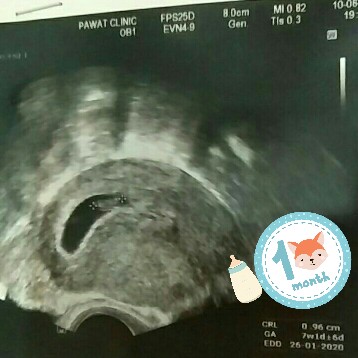

บ้านนี้7wเห็นประมาณนี้คะ ตอนนี้จะ14wแล้วคะ สู้ๆนะคะแม่ เดี๋ยวก็เจอน้องคะ

บ้านนี้ก็7สัปดาห์ เพิ่งไปซาวมาคับหมอบอกเล็กเท้าเม็ดถัวเขี้ยวคับ